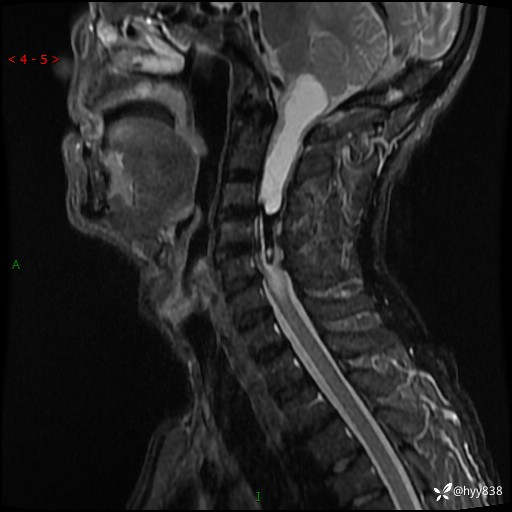

晨读典型病例分享。老年男性,右手麻木3年,四肢无力4月---结果公布~

主诉:右手麻木3年,四肢无力4月

简要病史:患者约于2年前无明显诱因出现右手麻木伴有精细活动差,无行走不稳,家属将患者送至当地县人民医院行颈椎MR提示:颈髓占位性病变。患者未系统治疗治疗。后病情逐渐加重,4个月前出现四肢无力,右侧为甚,行走不稳,伴有四肢感觉减退,伴有大便偶有失禁,现患者及家属为求进一步治疗入我院,遂以“椎管占位”收住我科。 发病以来,患者精神饮食睡眠好,大小便正常,体力体重未见明显改变。

辅助检查:MRI

临床诊断:椎管占位

颈椎MRI平扫(sag T1WI+T2WI-fs+axi T2WI)

CE